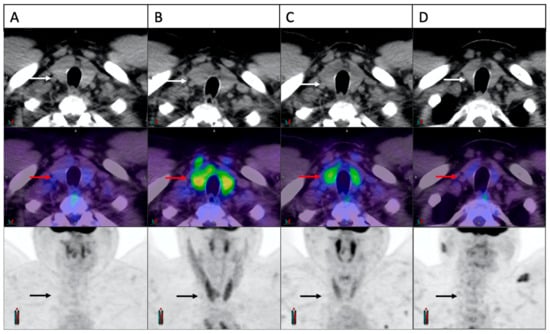

3.5. Concomitant Muscle Uptake